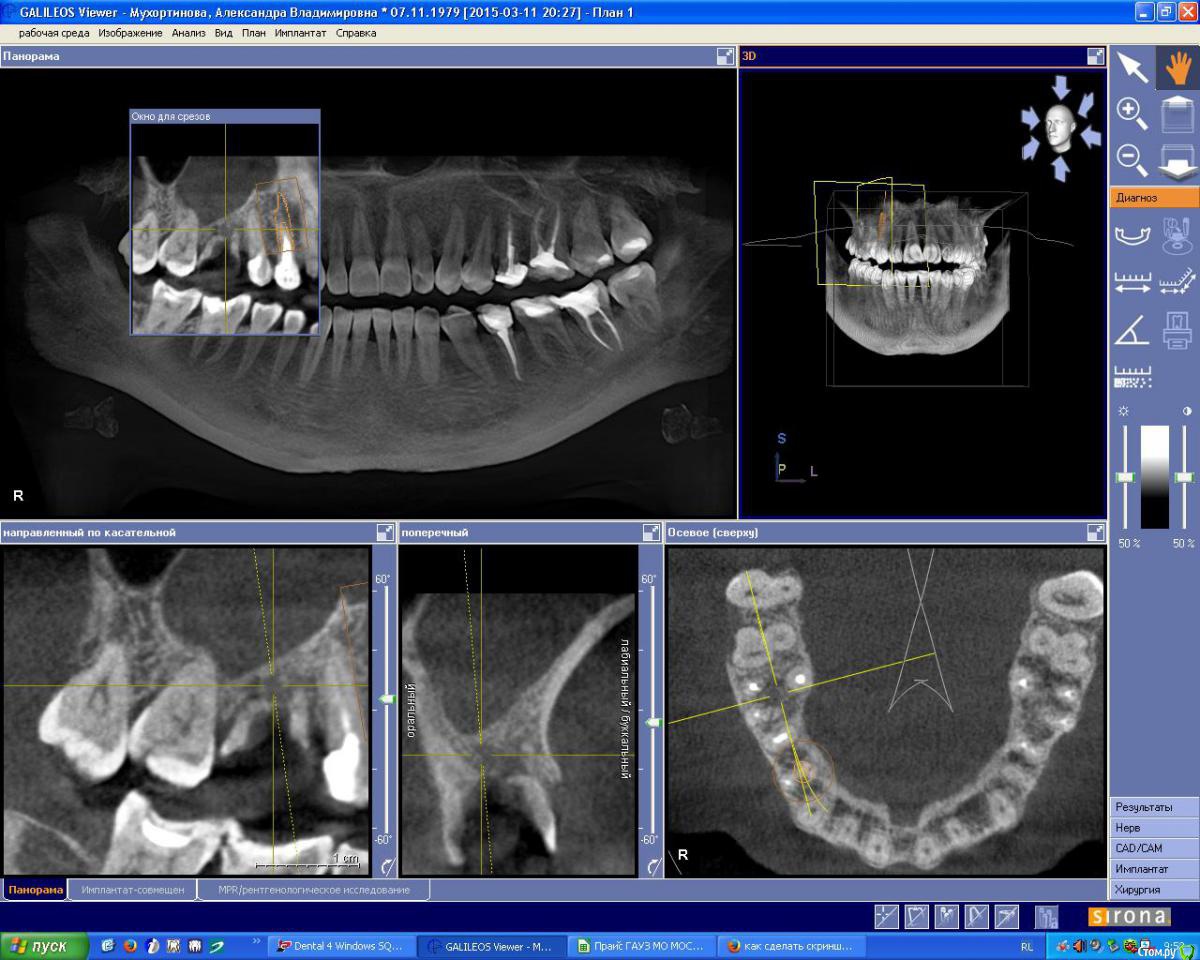

IshIm0 Опубликовано 8 июля, 2015 Поделиться Опубликовано 8 июля, 2015 (изменено) Добрый день. Пациентке Н. 2 недели назад ЛОР-врач удалил инородное тело из гайморовой пазухи справа (пломбировочный материал), который мигрировал в подглазничную область. Сейчас необходимо удалить зуб 16, пациентка хочет имплантат в последующем.Как всё правильно сделать ? Я думаю атравматично удалить зубик, аккуратно вычистить оставшийся пломбировочный материал в проекции дистально-щечного корня зуба 16 через лунку, подсыпать ксенокость, укрыть резорбируемой мембраной, через пол года установить имплантат в проекции 16 с одномоментным синус-лифтингом. Изменено 8 июля, 2015 пользователем IshIm0 Ссылка на комментарий

OLG Опубликовано 8 июля, 2015 Поделиться Опубликовано 8 июля, 2015 есть кистогранулёма в бифуркации Нет там кистогранулемы в фуркациия вижу резорбцию костной ткани по бифуркации.обычно резорбция костной ткани в бифуркации сопровождается наличием грануляционной ткани или кисты. (см. снимки 1 и 2) 1 Ссылка на комментарий

JIM Опубликовано 12 июля, 2015 Поделиться Опубликовано 12 июля, 2015 Пациентке Н. 2 недели назад ЛОР-врач удалил инородное тело из гайморовой пазухи справа (пломбировочный материал), который мигрировал в подглазничную область Что же ЛОР сказал об остальной части пазухи? Как-то по снимкам там не очень хорошо... Ссылка на комментарий